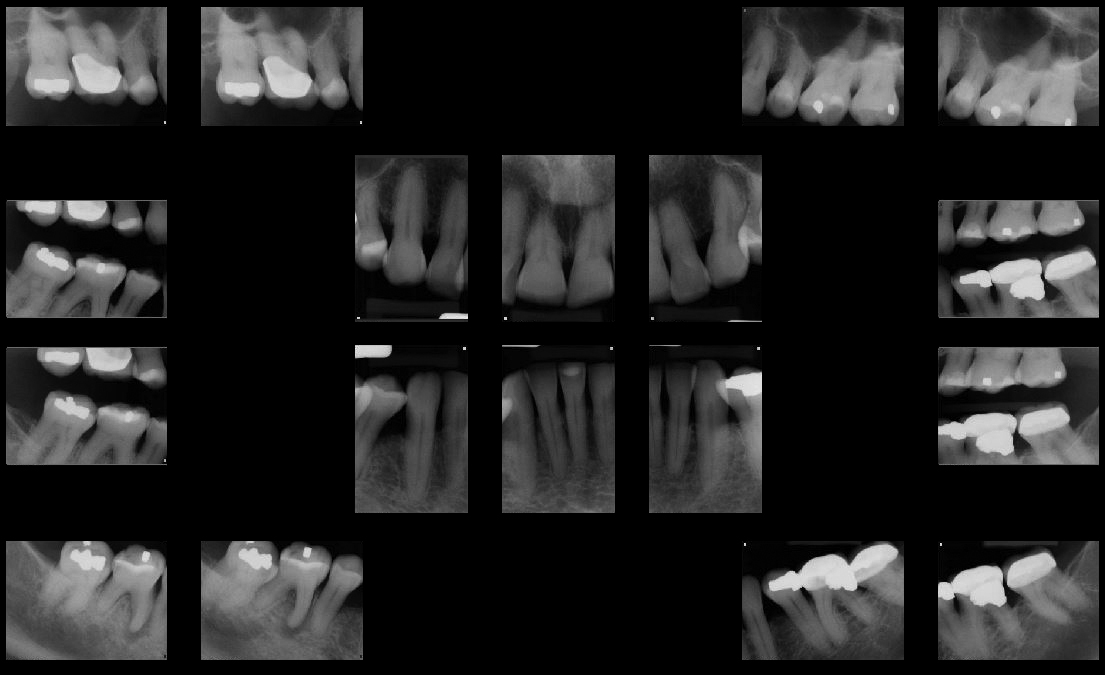

Phase II: Diagnostic Data Accumulation and Treatment Planning

Full Mouth Radiographic Series, Maxillary and Mandibular Intraoral Scans, Digital Jaw Relation Recording with a Leaf Gauge, Complete Photographic Series, Periodontal Charting, Restorative Charting.